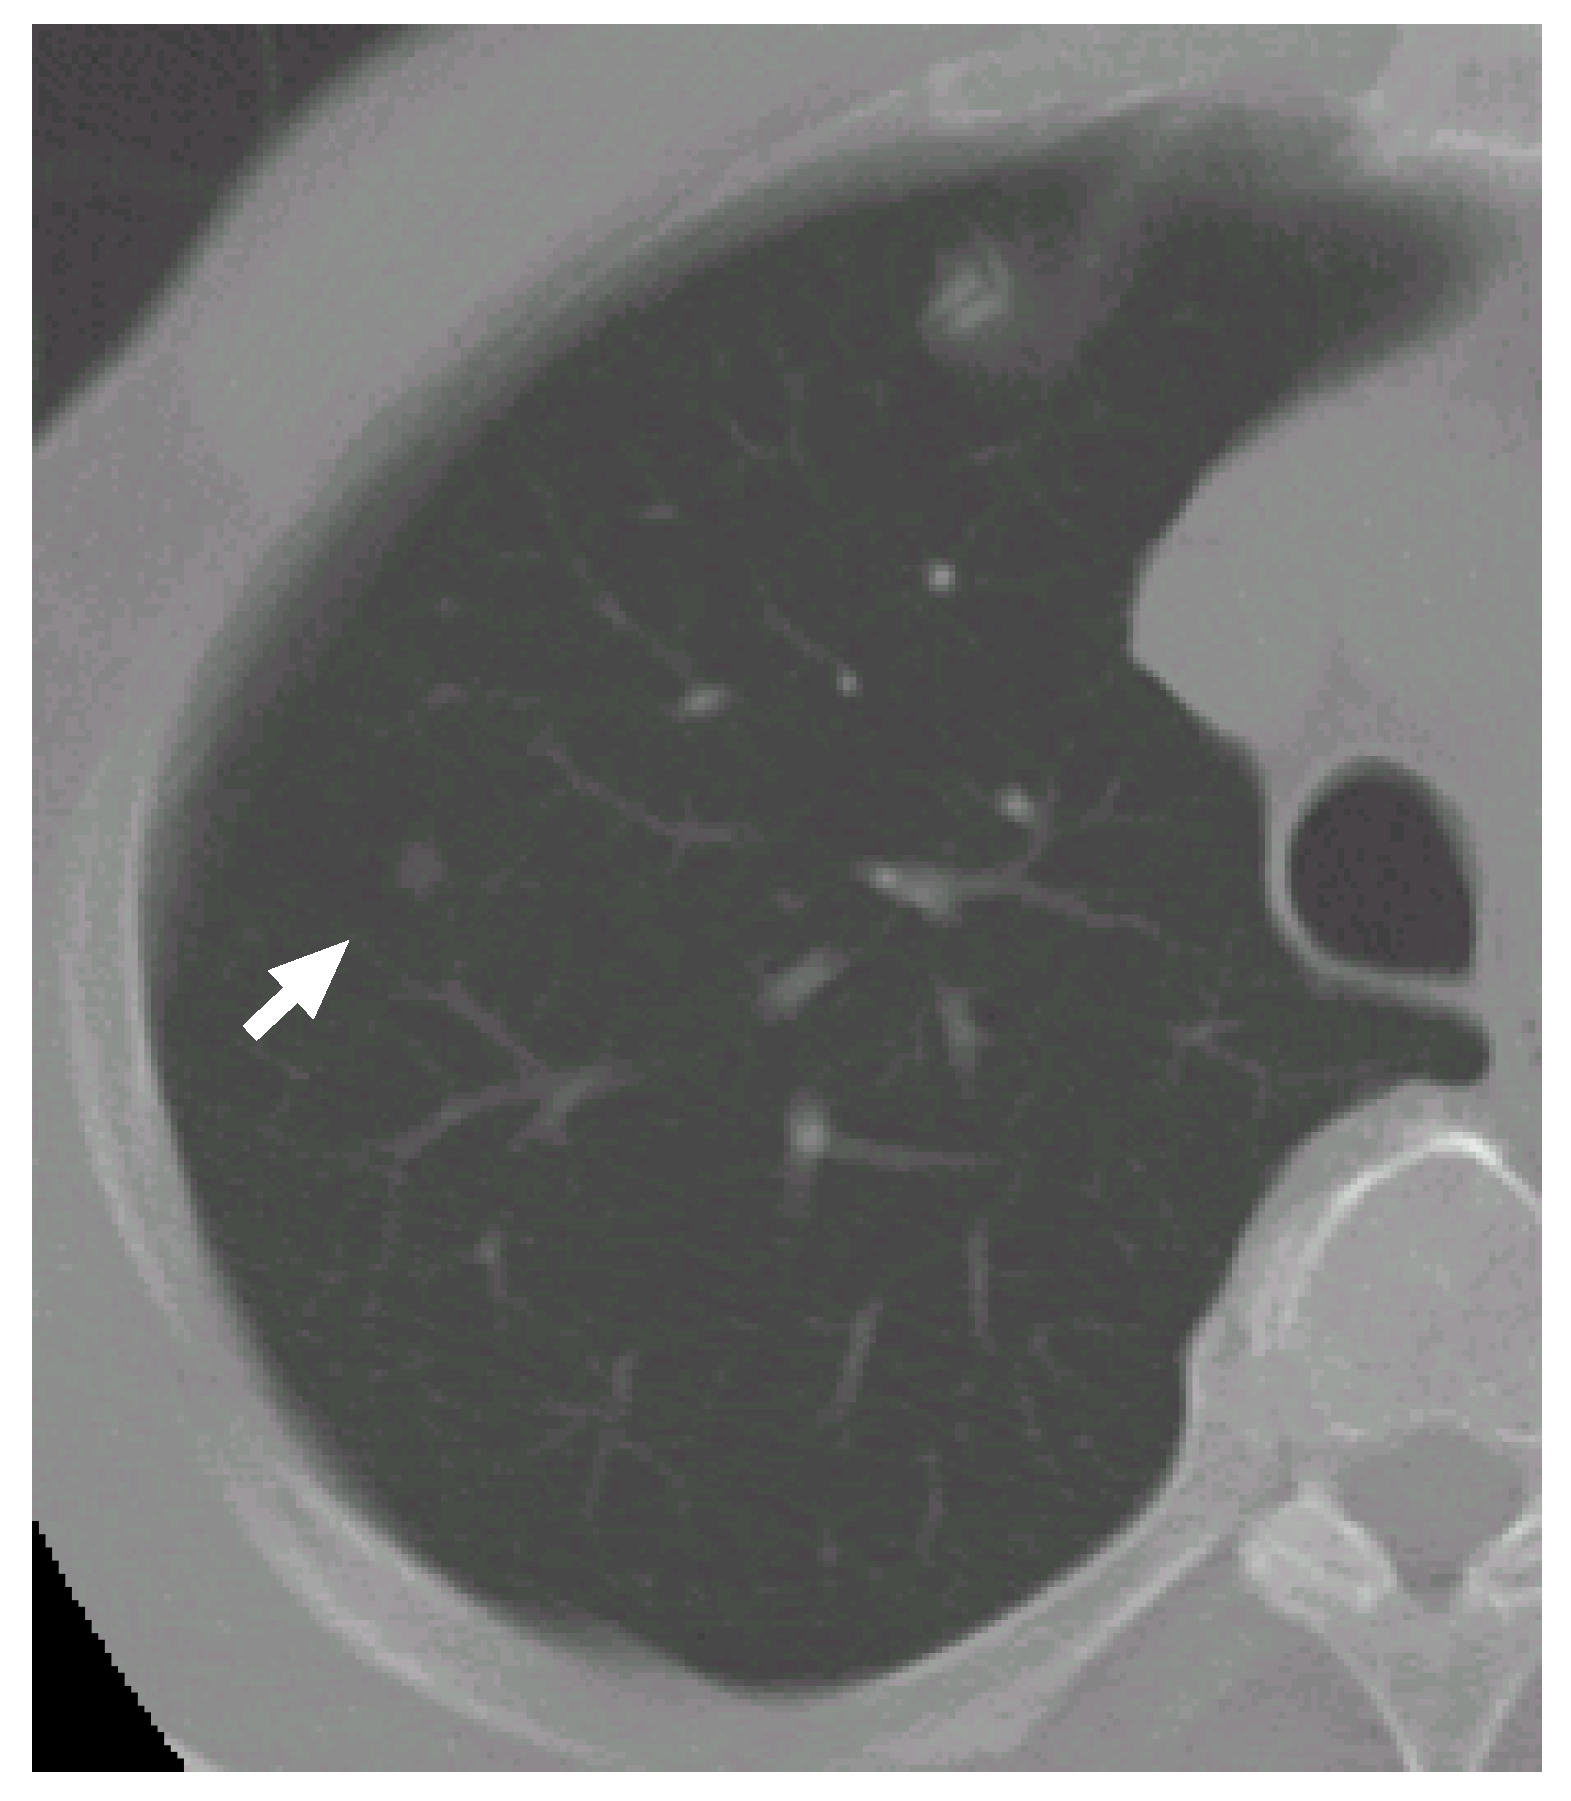

7.2. Case 2

Figure 9 shows another CT scan with a nodule. Figure 10 shows its VOI and templates, and Figure 11 the most likely object models. The posteriori probabilities are 0.121, 0.100 and 0.101, and the ratio is 1.20, that is larger than the threshold. Although the nodule is small (its diameter is approximately 3.8 mm), it is correctly determined to be a nodule.

Figure 9. The arrow indicates another nodule.